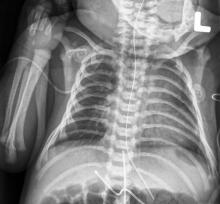

Most people have had an X-ray taken at some time during their lives — perhaps checking for a possible broken bone or during a visit to the dentist. X-ray exams provide important information to physicians about how to treat their patients. However, X-rays use ionizing radiation, and these imaging exams must be carefully and judiciously used on pediatric patients.